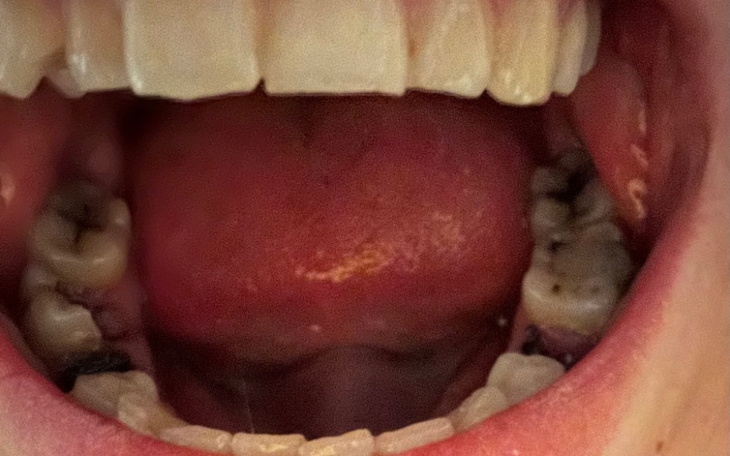

Cześć, jestem Ola i mój stan uzębienia jest w bardzo złym stanie. Od dzieciństwa miałam nieco utrudniony dostęp do dentysty. Moimi prawnymi opiekunami byli moi rodzice. Jednak mieszkałam z dziadkami. Babcia nawet pomimo zapewnień, że zapisuje mnie do dentysty nigdy tego nie robiła. Gdy wkroczyłam w dorosłość niestety wiedziałam już, że mój stan zębów jest fatalny i wstydziłam się bardzo iść do dentysty. Co oczywiście nie było dobrą decyzją - dzisiaj wiem, że wtedy jeszcze większość zębów można było wyleczyć w ramach NFZ. Dzisiaj mam 27 lat i odważyłam się dopiero miesiąc temu udać się do dentysty w ramach doraźnej pomocy. Niestety lekarz uświadomił mnie, że w moim przypadku leczenie musi być w większości prywatne. Większość zębów trzeba leczyć kanałowo lub wyrwać. Wiecie dlaczego po tylu latach poszłam do dentysty? Spuchłam przez noc, nie czułam nawet bólu, ale strasznie się przestraszyłam, że jest to angina Ludwiga.

Mam cudowną 2 letnią córkę i naprawdę mam dla kogo żyć. Ale bardzo błądziłam w przeszłości i do dnia dzisiejszego mam kredyty, które spłacam oczywiście regularnie, ale nie stać mnie przez to na wydanie więcej niż 100 zł miesięcznie na dentystę. Jeszcze nie podjęłam żadnych działań, ale każda złotówka ze zbiórki byłaby oczywiście rozliczona. Chciałabym po prostu mieć na tyle zdrowe zęby, by nie obawiać się przedwczesnej śmierci.